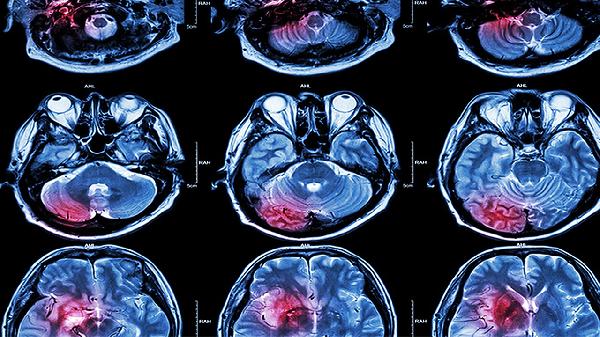

老年人容易脑溢血主要与血管老化、高血压、动脉硬化、脑血管畸形及抗凝药物使用等因素有关。脑溢血通常表现为突发头痛、呕吐、意识障碍等症状,严重时可危及生命。